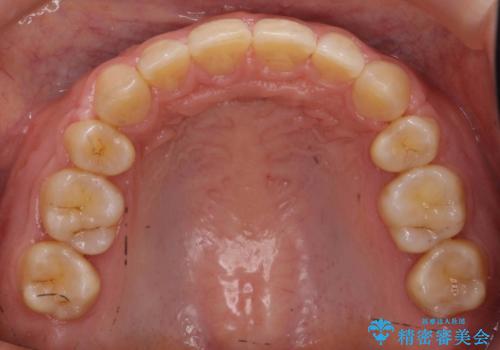

前歯のすきま 右上の小臼歯の垂直的骨吸収を抜歯で解決

- 前歯のすきまを気にして来院。

奥歯が1歯対1歯で、過蓋咬合を呈していました。

short faceであり、結果上顎の臼歯を近心に大きくロスさせることになったたため、非常に長く治療期間はかかりました。